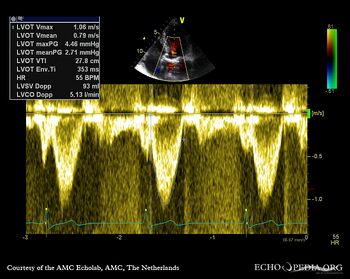

Continuous-wave Doppler signal of transaortic flow Pulsed-wave Doppler signal of flow in left ventricle outflow tract